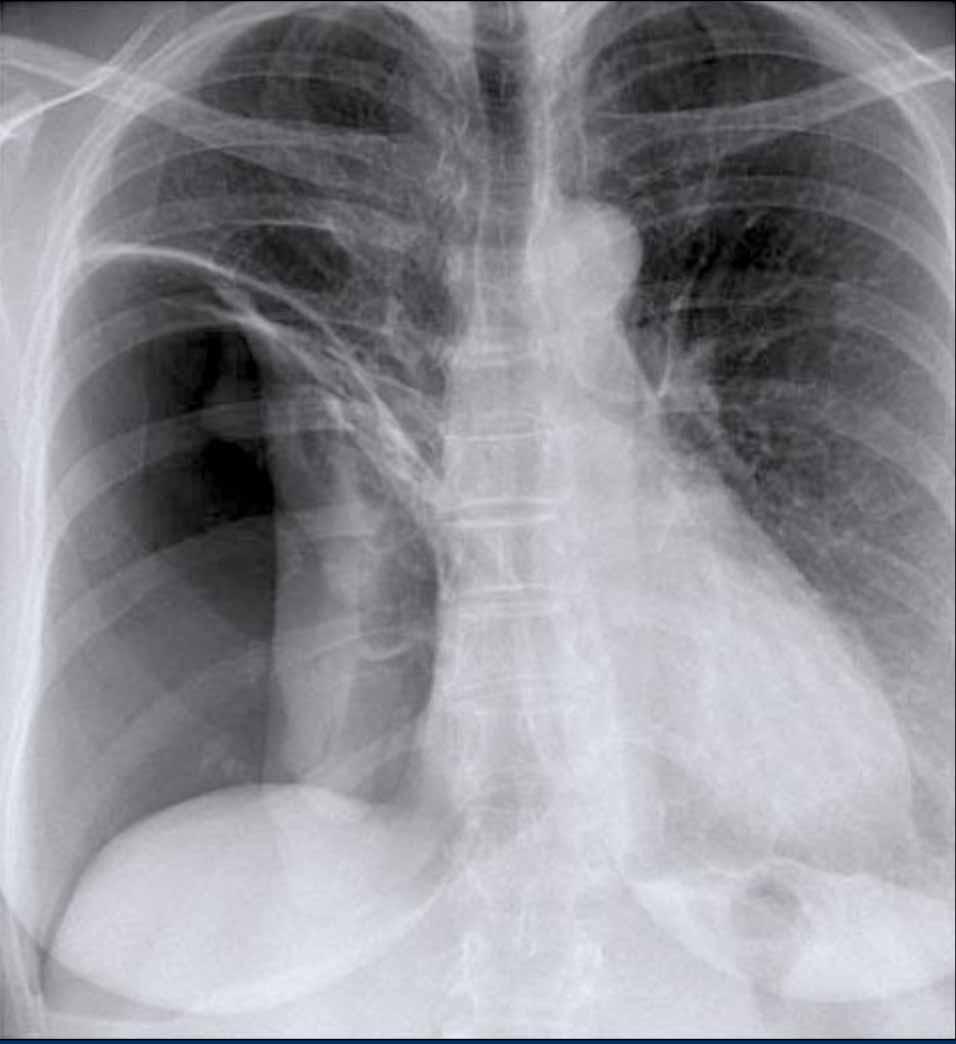

Ví dụ Lâm sàng: Dấu hiệu Kín đáo của Suy tim Sung huyết

Hãy bắt đầu bằng cách xem xét các phim X-quang ngực hiện tại.

Chỉ dựa trên các hình ảnh này, người đọc có thể nghi ngờ suy tim sung huyết (CHF), mặc dù các dấu hiệu còn khá kín đáo.

Bây giờ hãy xem lại phim cũ trước đó…

Việc cuộn qua lại giữa phim hiện tại và phim cũ giúp tăng đáng kể độ tin cậy trong chẩn đoán suy tim sung huyết.

Các dấu hiệu so sánh chính bao gồm:

- Kích thước tim: Tăng nhẹ so với phim trước; tuy nhiên, tim to đã hiện diện từ trước.

- Hệ mạch máu phổi: Cương tụ mạch máu nhẹ gợi ý tăng áp lực tĩnh mạch phổi.

- Hình ảnh mô kẽ: Dấu hiệu kín đáo của phù mô kẽ.

- Tràn dịch màng phổi: Tràn dịch lượng ít hai bên, với thay đổi kín đáo ở bờ dưới-sau của các thùy dưới, gợi ý tích tụ dịch.